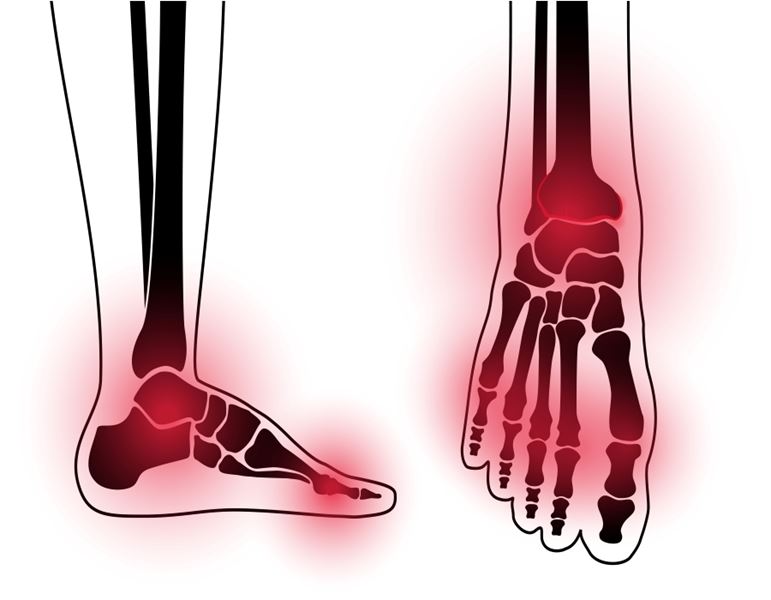

למידע נוסף על טיפול אלקטרומגנטי לדורבן בעקב לחצו !

למידע נוסף על טיפול אלקטרומגנטי לשחיקת סחוסים לחצו !